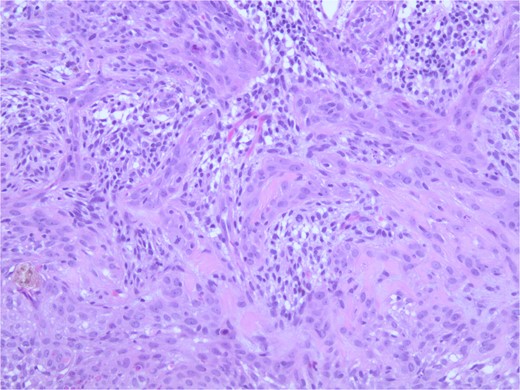

At the time of the surgery, the lesion was excised with 5 mm margins, given the acceptable margins of 4 mm for nonmelanoma skin cancer [4]. Macroscopic examination of the lesion revealed a well-defined, hyperpigmented, macular lesion with pathology positive for infiltrating BSC with negative margins confirmed on histology. Histology was notable for predominantly basal cell morphology with areas of squamous differentiation. The presence of the basal cell carcinoma component is demonstrated (Fig. 1). The BSC with abnormal squamous keratinization is also demonstrated (Figs 2–4). These studies were conducted on routine hematoxylin and eosin stains confirming the diagnosis of BSC. The patient was seen in the office, and at 2 months postoperative, there were no clinical concerns.

Microphotograph revealing basal cell carcinoma component on histology.